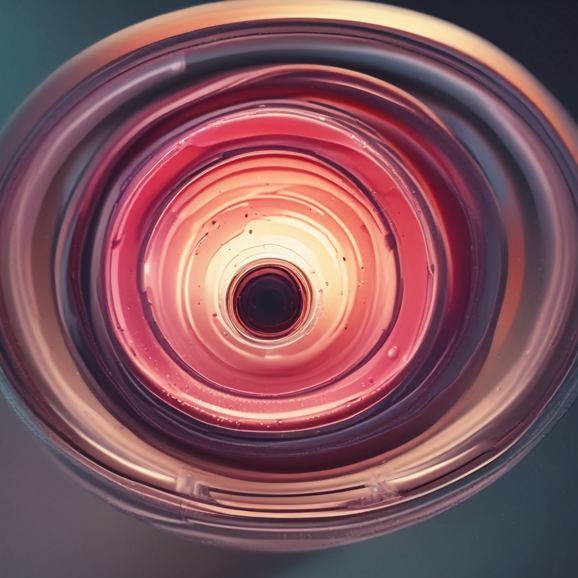

Innovazione diagnostica e soluzioni ortopediche.

Lavoriamo nella distribuzione di dispositivi medici innovativi per la diagnostica del linfonodo sentinella e per la diagnostica epatologica grazie alla nostra avanzata innovazione nella tecnologia di elastografia epatica, . Offriamo soluzioni personalizzate per ortopedia sia come tutori che come CAST alternativi al gesso da frattura